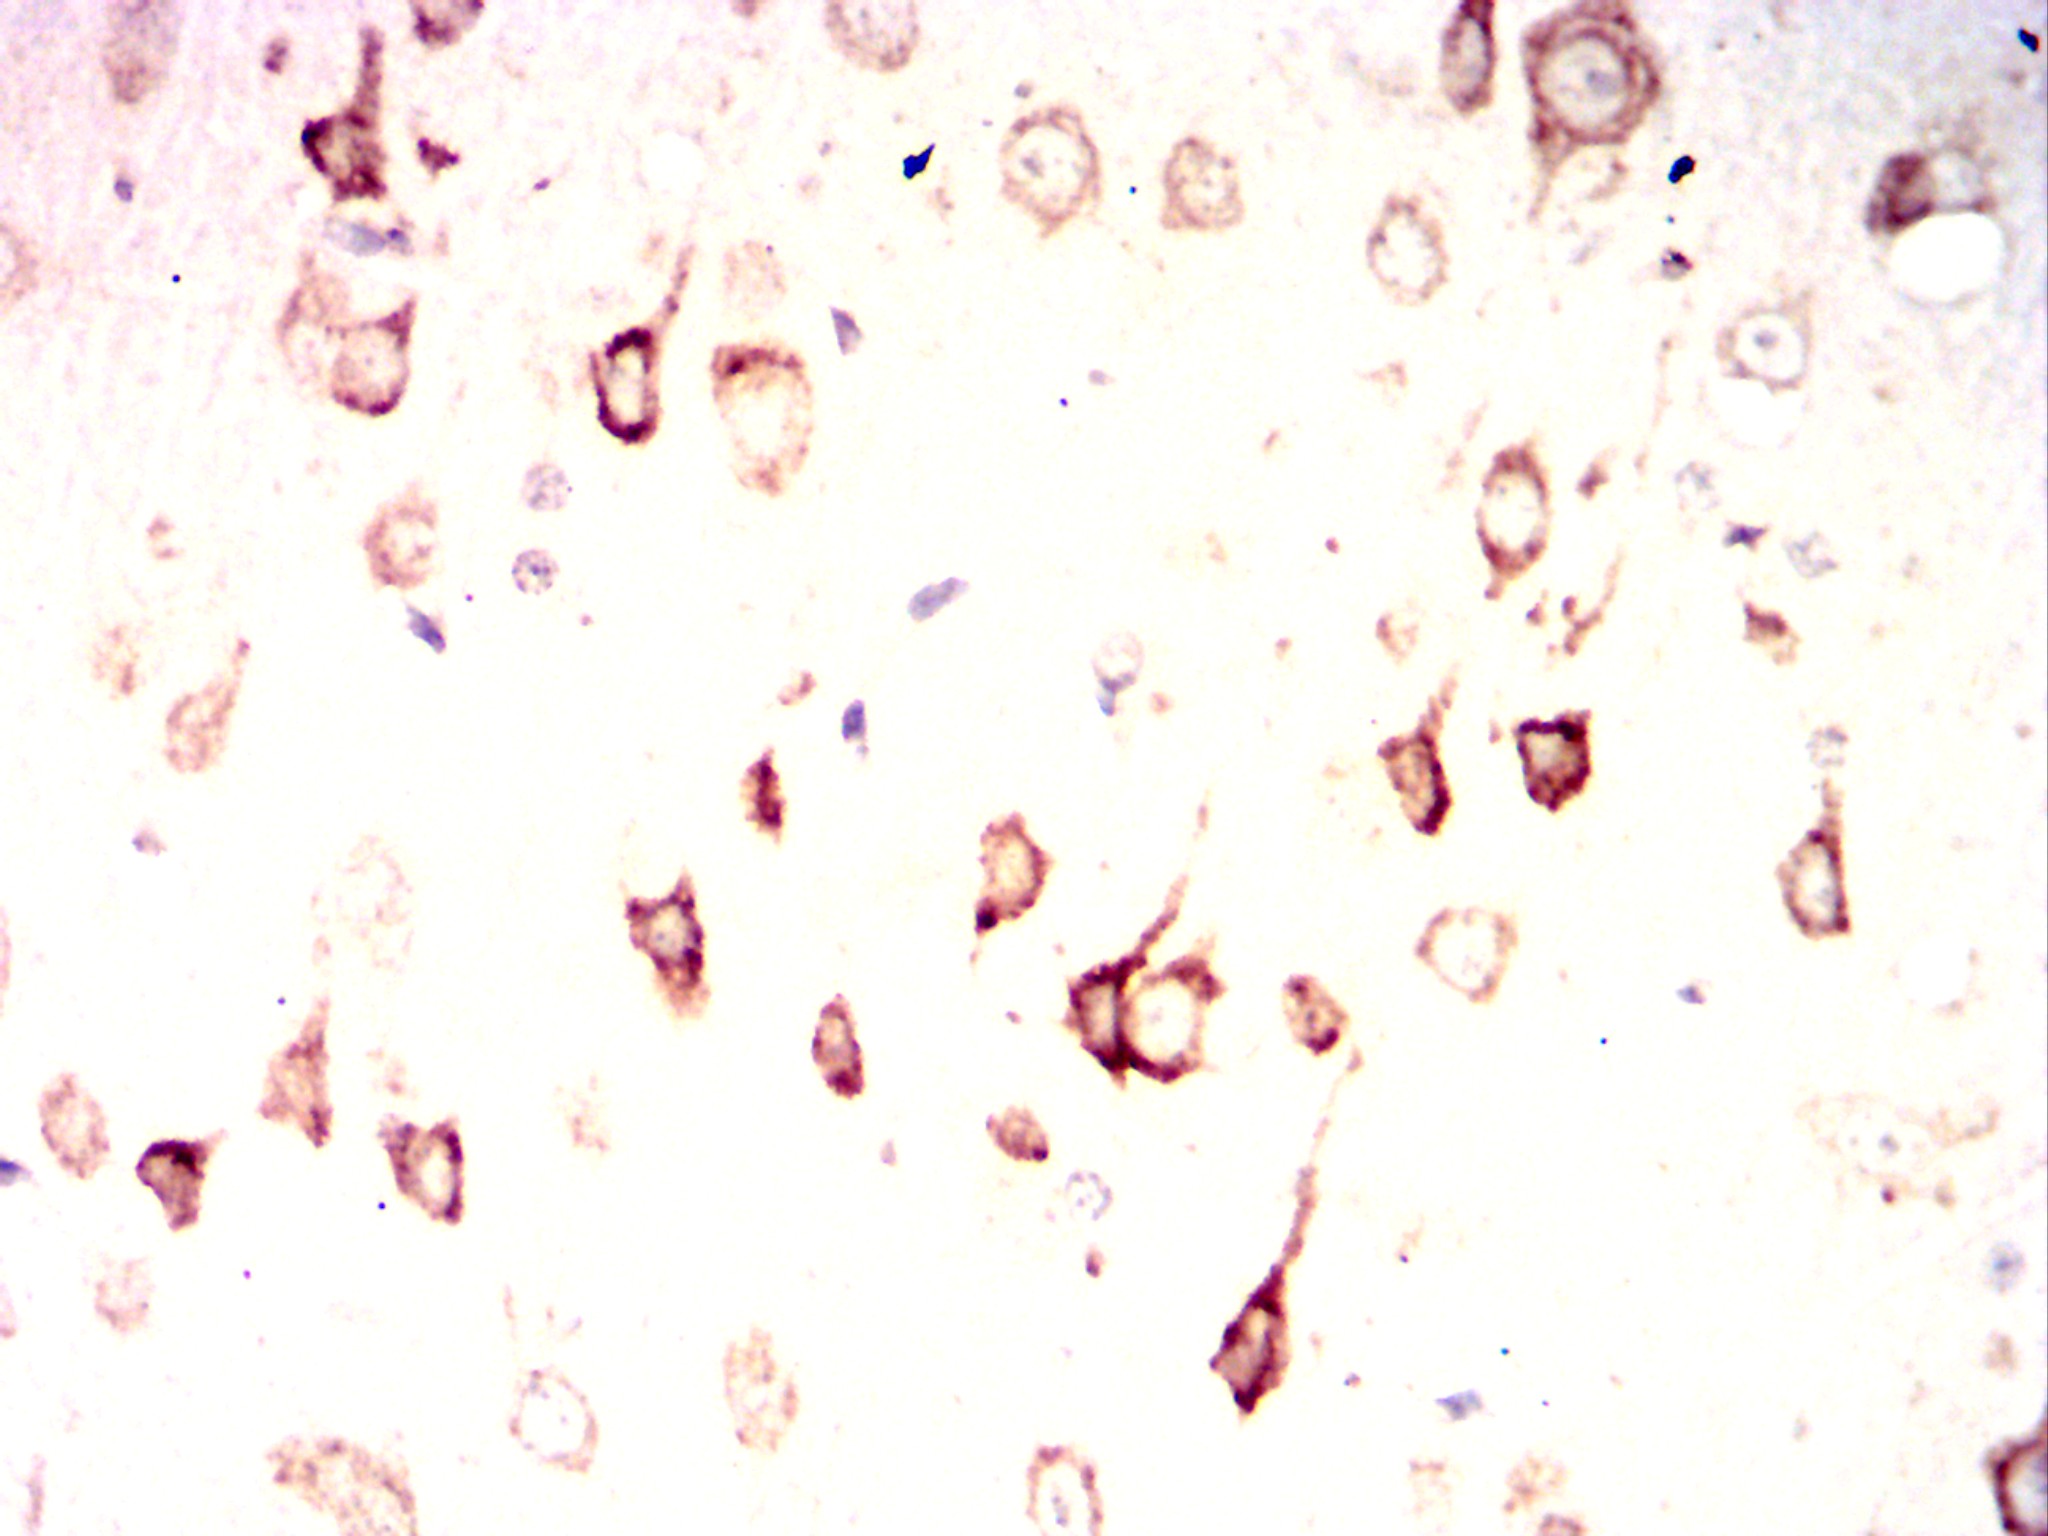

IHC 1/50-1/500 Human,Rat

Product Image